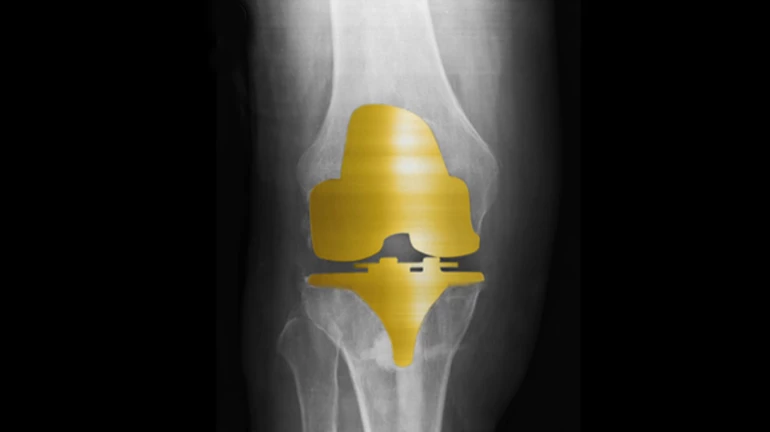

This surgery is now available in a small number of hospitals in India. During this surgery, a part of 'knee implant' i.e tetanial neobium nitrate is covered with a golden-like colour and hence this surgery is known as 'Golden Knee Replacement'.